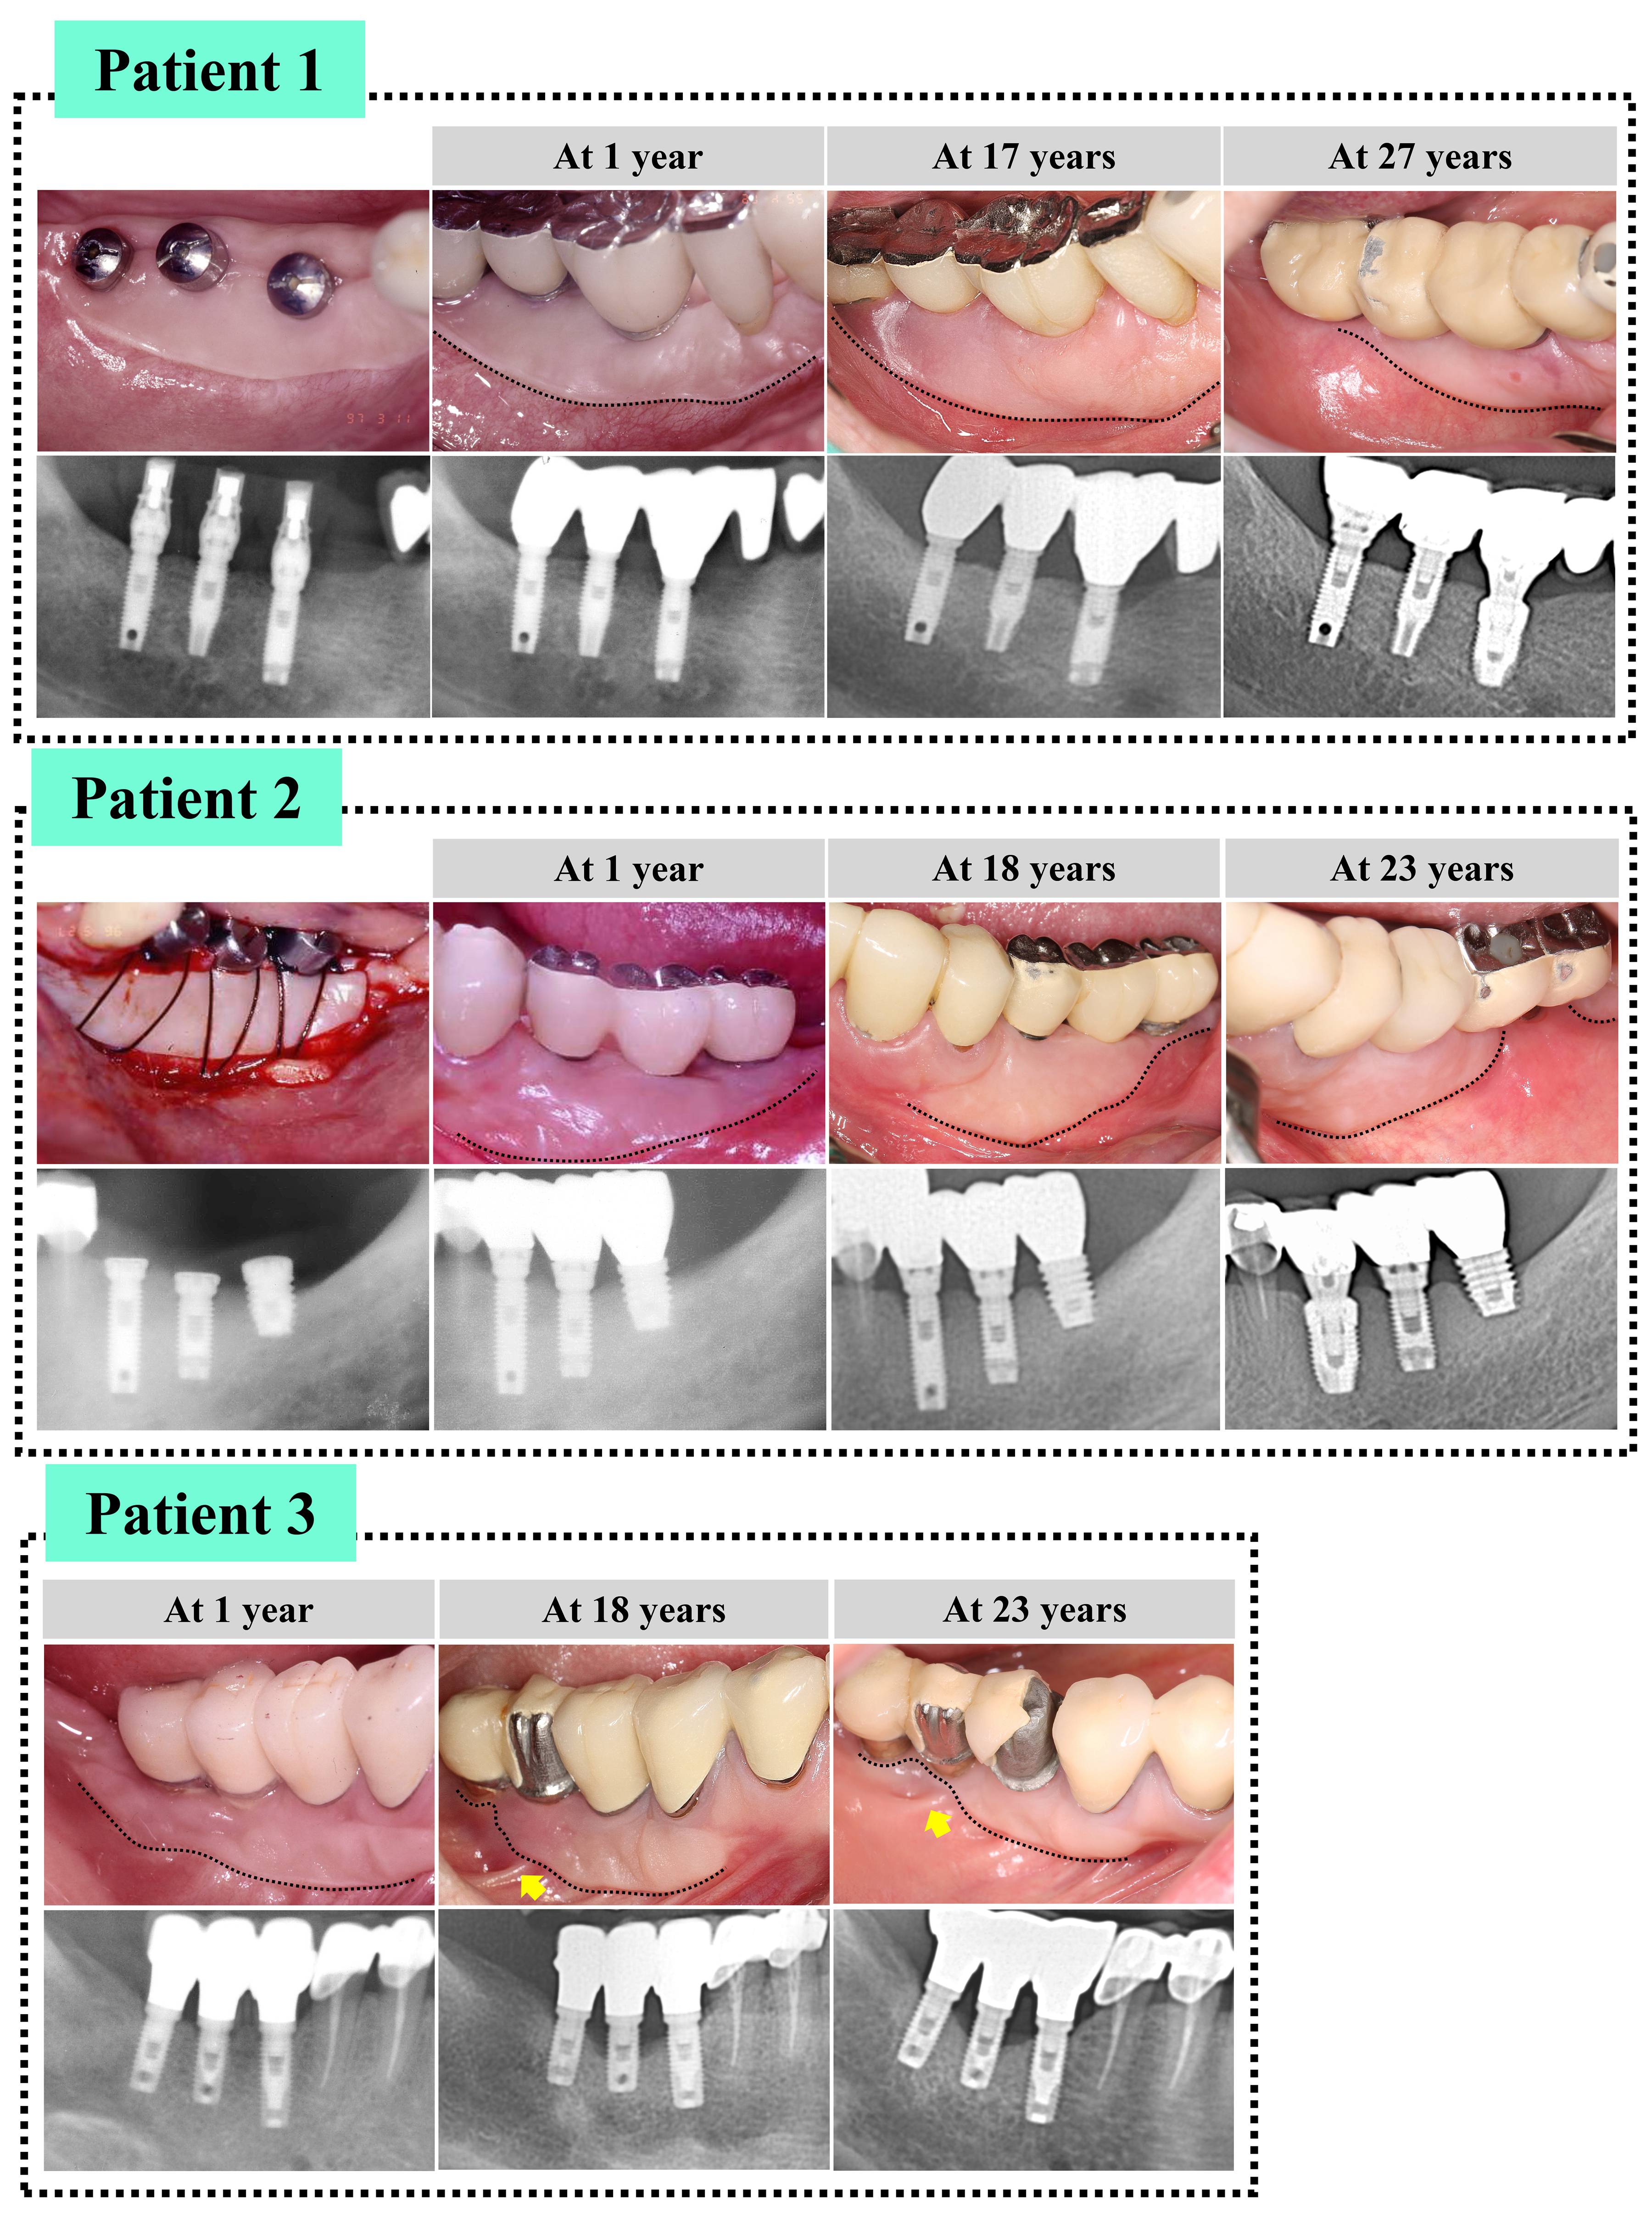

- Several studies have suggested that peri-implant keratinized mucosa (PIKM) is related to peri-implant health. Thus, PIKM augmentation, such as free gingival grafting …

- Several studies have suggested that peri-implant keratinized mucosa (PIKM) is related to peri-implant health. Thus, PIKM augmentation, such as free gingival grafting (FGG), is often performed to re-establish the keratinized tissue zone. Implant sites may influence the long-term stability of the re-established PIKM; however, relevant data are insufficient. In three patients, three implants were placed in areas with missing first and second mandibular molars. To create the PIKM zone, an FGG was used. During the follow-up (≥20 years), the re-established PIKM at the distal site in the posterior mandible showed greater reduction than at the mesial site, indicating site-specific stability characteristics. Some implants present with unfavorable bone remodeling and peri-implant diseases, and these conditions seem to contribute to PIKM stability by forming unattached parts of the PIKM. The findings of this study should be verified in a larger patient population with healthier conditions. - COLLAPSE